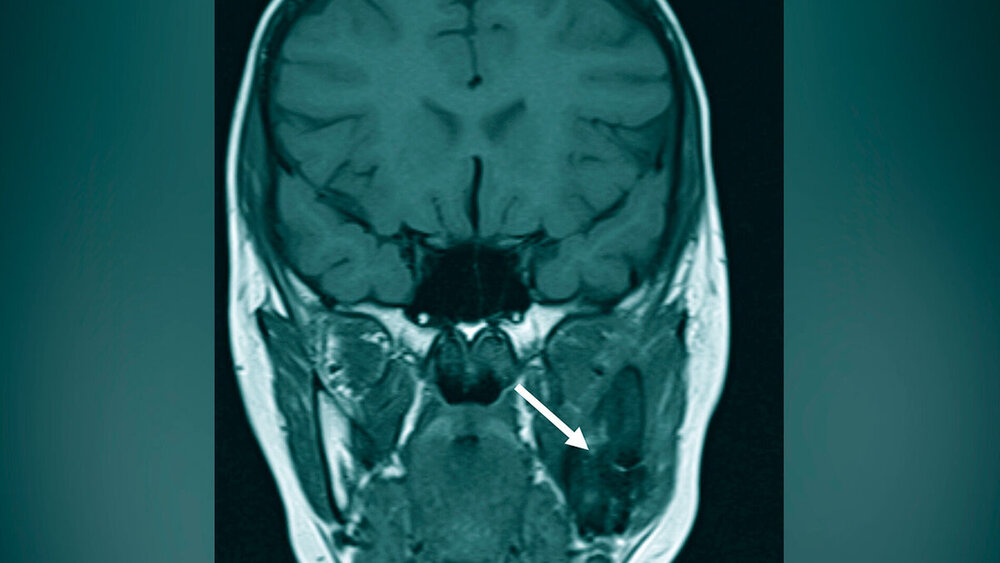

Zur (differenzial-)diagnostischen Beurteilung und Darstellung der Befundausdehnung wurde zunächst unter Berücksichtigung des Kindesalters eine Bildgebung mittels Magnetresonanztomografie (MRT) durchgeführt. Diese zeigte in der T1-Wichtung im Bereich des linken Kieferwinkels lokalisierte diffuse, inhomogene und signalarme Strukturen mit expansiver Auftreibung der Kortikalis und entzündlicher Begleitreaktion der angrenzenden Muskulatur (Abbildung 1). Aufgrund der MRT-morphologisch nicht zweifelsfrei wegweisenden Befunde erfolgte zur genaueren Beurteilung des knöchernen Gesichtsschädels eine ergänzende Computertomografie (CT), die kongruent zu den signalarmen Bereichen in der MRT milchglasartige Volumenvermehrungen des linken Kieferwinkels mit Ausbreitung in den Processus coronoideus und ins angrenzende Collum mandibulae aufwies (Abbildung 2). Die durchgeführte CT stützte bei den oben genannten, charakteristischen Kriterien (Abbildung 3) im Kontext der klinischen Befunde die Arbeitsdiagnose der fibrösen Dysplasie.